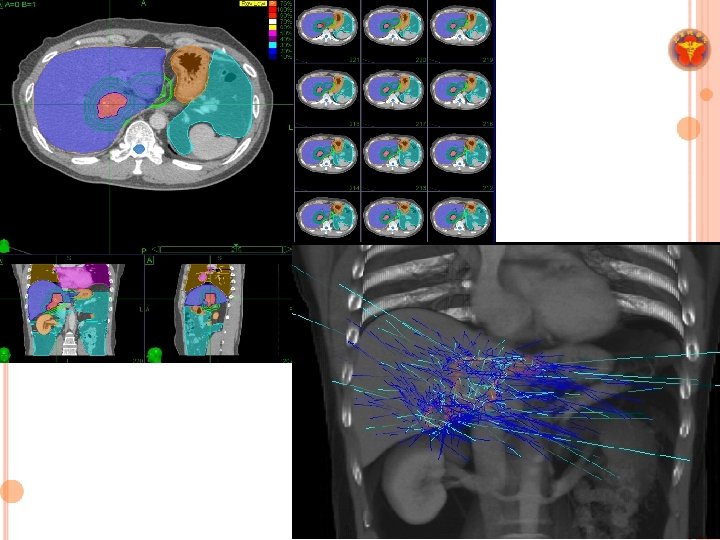

RADIOTHERAPY IN LIVER TUMORS ¢ RT was not standard treatment for liver cancer. ¢ Limitation: * poor radiation tolerance of normal liver * organ motion

SABR FOR LIVER CANCER INTSGH ¢ Research overview 1. Indications (safety and efficacy) (1) Recurrent HCC (Int J Radiat Oncol Biol Phys 2012) (2) TACE-failed HCC (European Journal of Gastroenterology & Hepatology 2014) (3) Re-irradiation for HCC (Journal of Gastroenterology and Hepatology 2014) 2. Identify prognostic indicators (1) 18 F-FDG PET parameters (J Nucl Med 2013) 3. Image response evaluation (1) Radiographic response evaluation for PVTT (Therapeut Radiol Oncol 2016) (2) Functional image biomarker (DWI) (Ongoing) 4. Other than HCC (1) SABR for Cholangiocarcinoma (2017 Tumori, Epub) 5. Development and validation of nomogram for treatment outcome (1) For BCLC stage C disease (International study under ALRT SIG) SIG 6. Immunological biomarkers before and after SABR (1) Tim-3, PD 1, PD L 1 (ongoing)

MATERIALS &METHODS ¢ A retrospective cohort study ¢ Between December 2007 and July 2015 ¢ BCLC stage C disease ¢ Child-Turcotte-Pugh class A–B